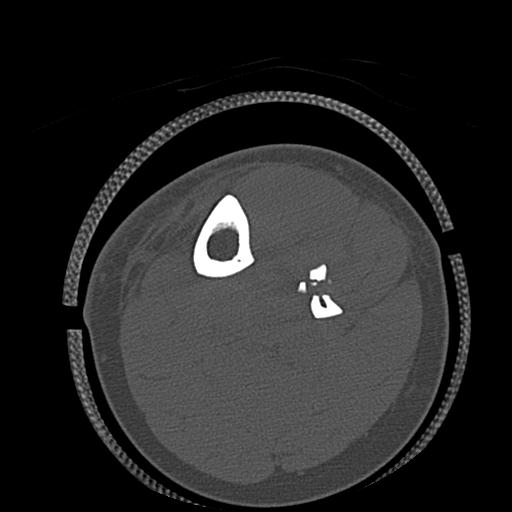

102755 1/4 2R 1/15 2R 右足関節 68歳女性 右三果脱臼骨折